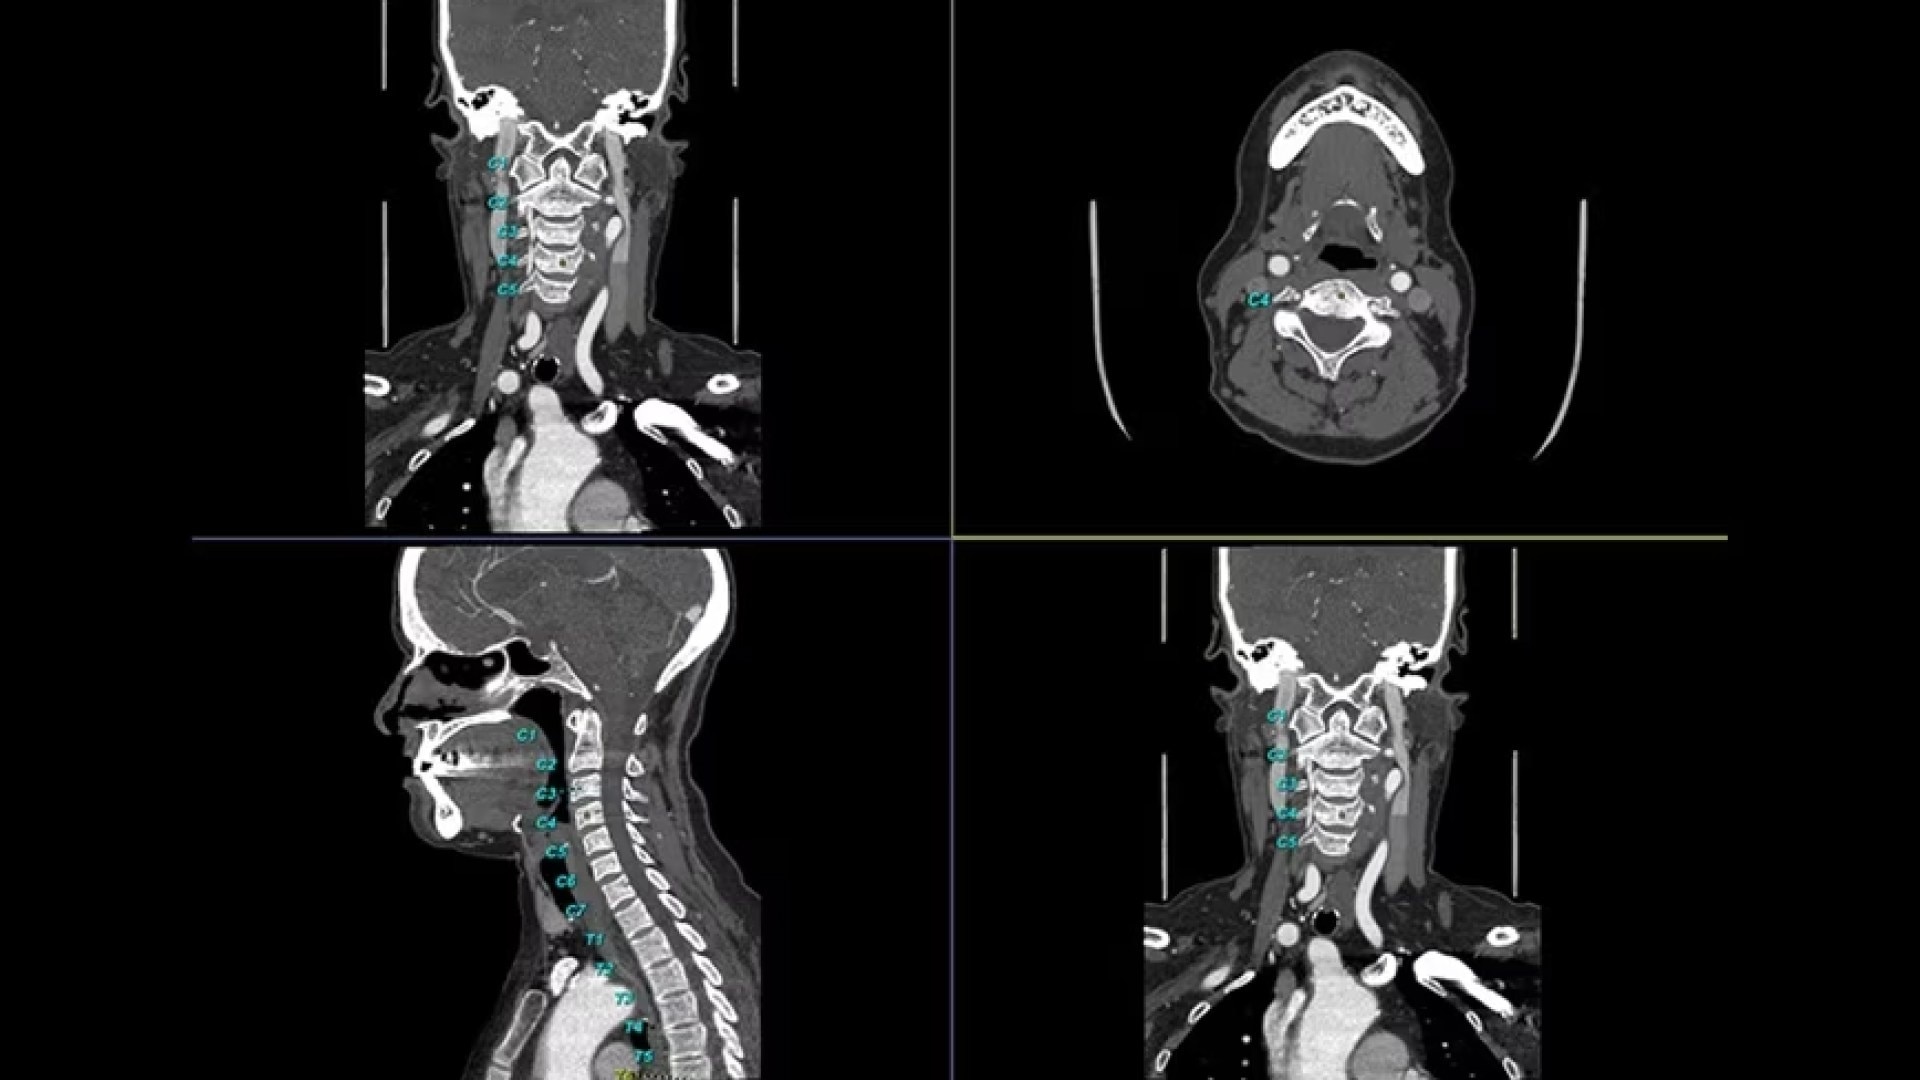

Bone VCAR

Spine assessment with deep-learning based CT application.

Automated curved reformats to aid in rapid reading and reporting.

• Automated generation of a 3D trace to generate oblique and straightened reformat views

• Automated generation of oblique views perpendicular to vertebral bodies and disc spaces

• Accessible for any exam type: trauma, oncology, dedicated spine, general imaging